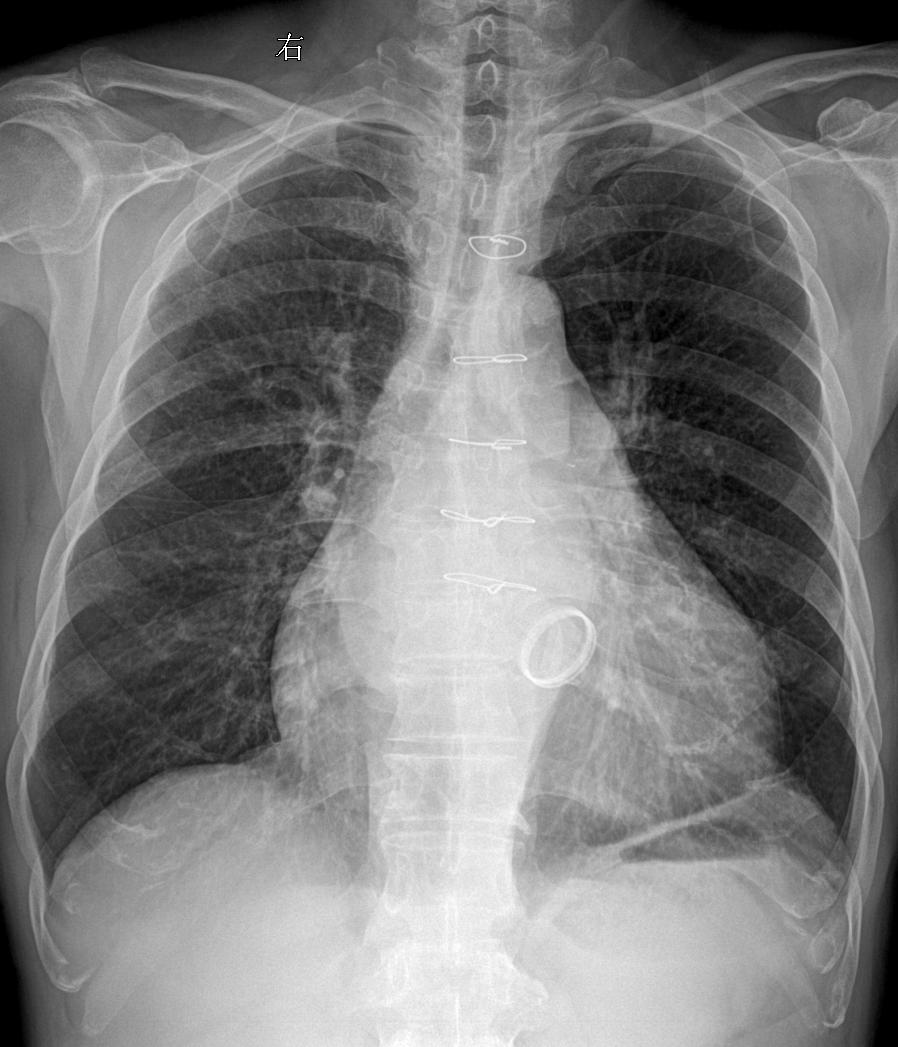

术后胸闷就诊 考虑什么?家银们